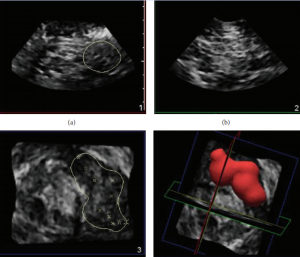

Start 4D and select the 4 panel view showing transverse, longitudinal, coronal, and volume view. With the MPR crosshair set to partial, adjust the crosshair so that it lies over the tip of the needle in the transverse, longitudinal, and coronal view.

Draw back on the syringe to ensure that the needle is not intravascular and inject a test dose of local anesthetic. Confirm that the local anesthetic spreads appropriately by enveloping the nerve. Inject the total volume if a single dose nerve block is desired or 2/3 of the total local anesthetic dose if inserting a catheter. The spread of the local anesthetic in all four planes (transverse, longitudinal, coronal, and 3D volume) will be seen and the nerve should now be clearly visible due to the fluid-nerve interface.

In Q-lab, adjust the threshold to better visualize the fluid/tissue interface. Press “calliper” on the touch screen and outline the local anesthetic spread with the ellipse tool. Use the track ball to adjust the calliper and measure the diameter of the fluid space. The volume calculation appears on the screen.